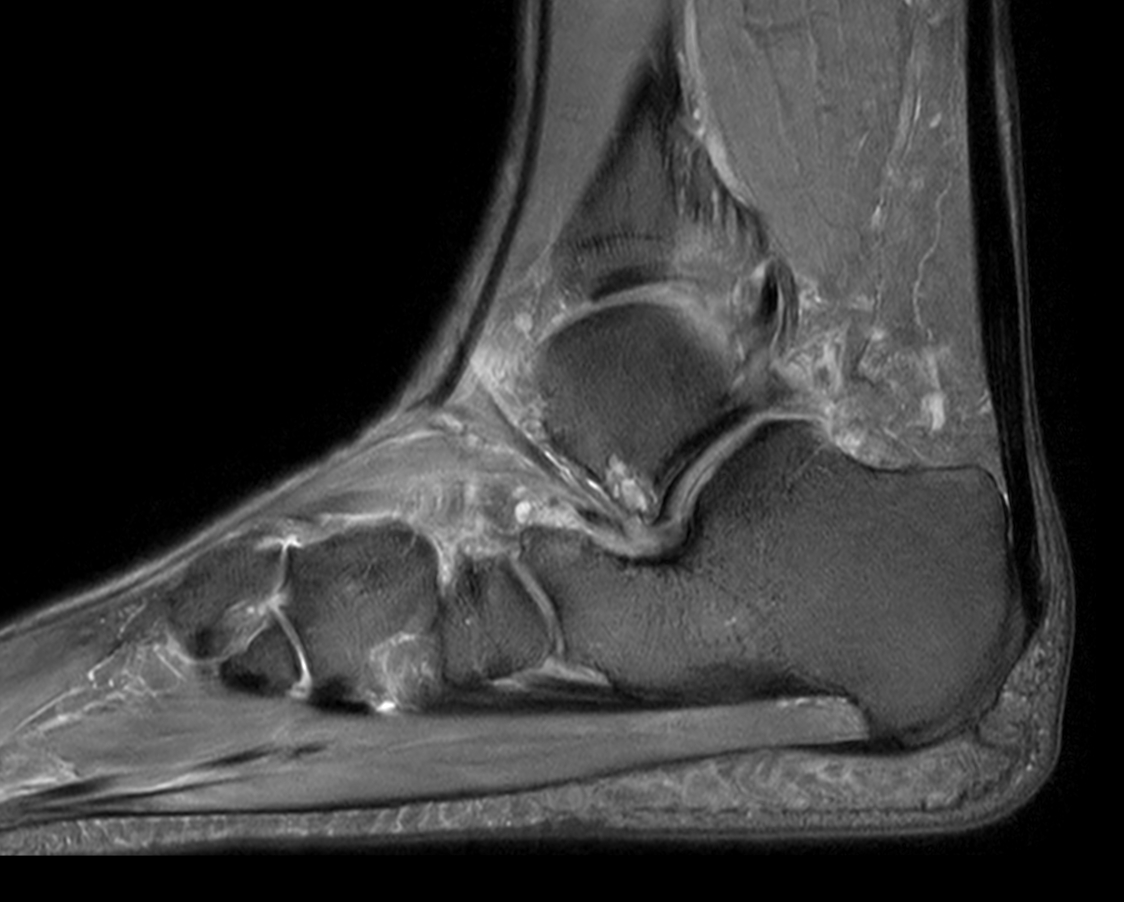

Sagittal 3D PDw MSK VIEW